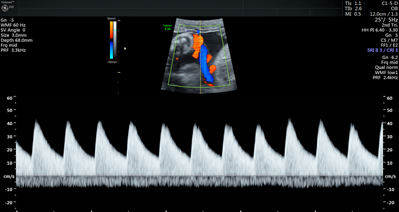

Currently, standard-of-care ultrasound scans measure blood flow at one point in the umbilical cord. The technique developed by Sled and his collaborators takes two measurements – one at the fetal end of the umbilical cord and one at the placental end. Sled says recording both measurements gives a much more accurate picture of the way blood is travelling through the umbilical cord.

“By looking at both measurements and the physics of how blood travels, we can get insight into how some of the finest blood vessels in the placenta are organized. The information this can provide to physicians is invaluable,” says Sled, who is also the Director of the Mouse Imaging Centre and a Professor and Vice-Chair in the Department of Medical Biophysics at the University of Toronto.